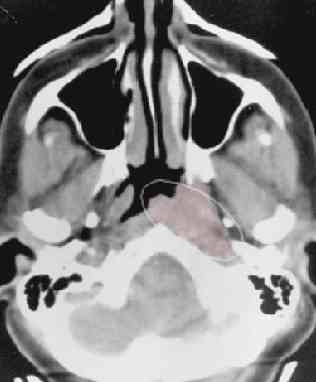

CT normal anatomyCTCTpic#1 and pic#2, CT advanced nasopharynx cancer